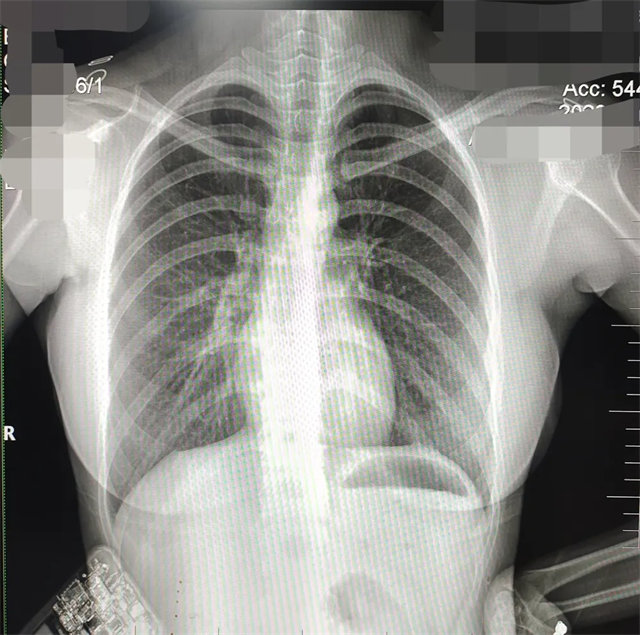

缺陷:左肩胛骨部分與左肺野重疊。

解決:使患者左肩旋前緊貼成像件重新曝光。